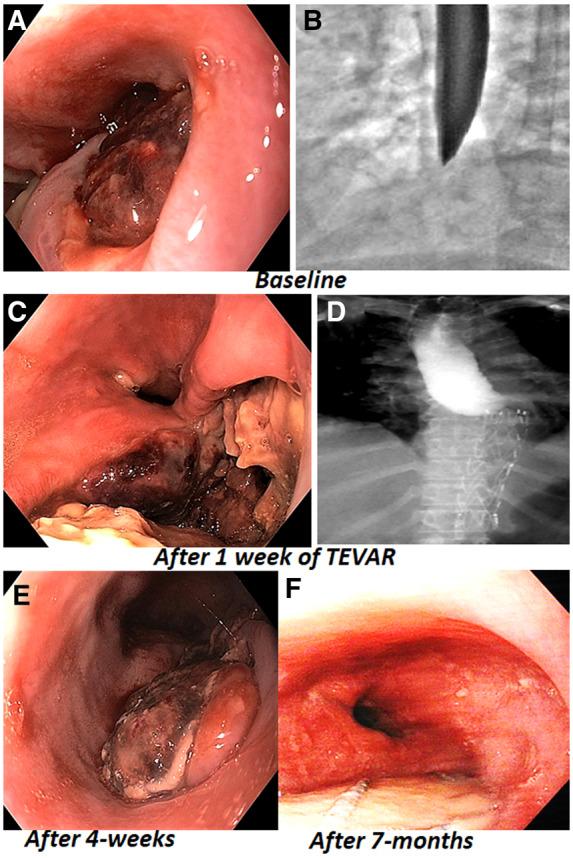

We hereby report two cases of AOF, who underwent successful emergency thoracic endovascular aortic repair (TEVAR) to control active bleed and exsanguination. Case 1, an elderly lady with atherosclerotic aneurysm had TEVAR followed by open surgery for oesophageal rent and necrosed left main bronchus. Case 2 had mycotic tubercular aneurysm who later had infected graft-stent following TEVAR.

我们在此报告两例AOF患者,他们成功接受了急诊胸主动脉腔内修复术(TEVAR)以控制活动性出血和失血。病例1是一位患有动脉粥样硬化性动脉瘤的老年女性,接受了TEVAR治疗,随后进行了食管裂口和左主支气管坏死的开放手术。病例2患有霉菌性结核性动脉瘤,在TEVAR后出现了感染的移植物支架。